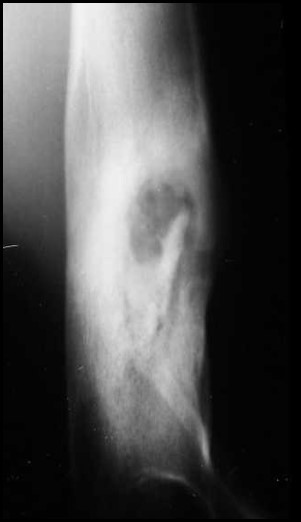

Discuss this radiograph

Bone infection – surrounding has increased opacity